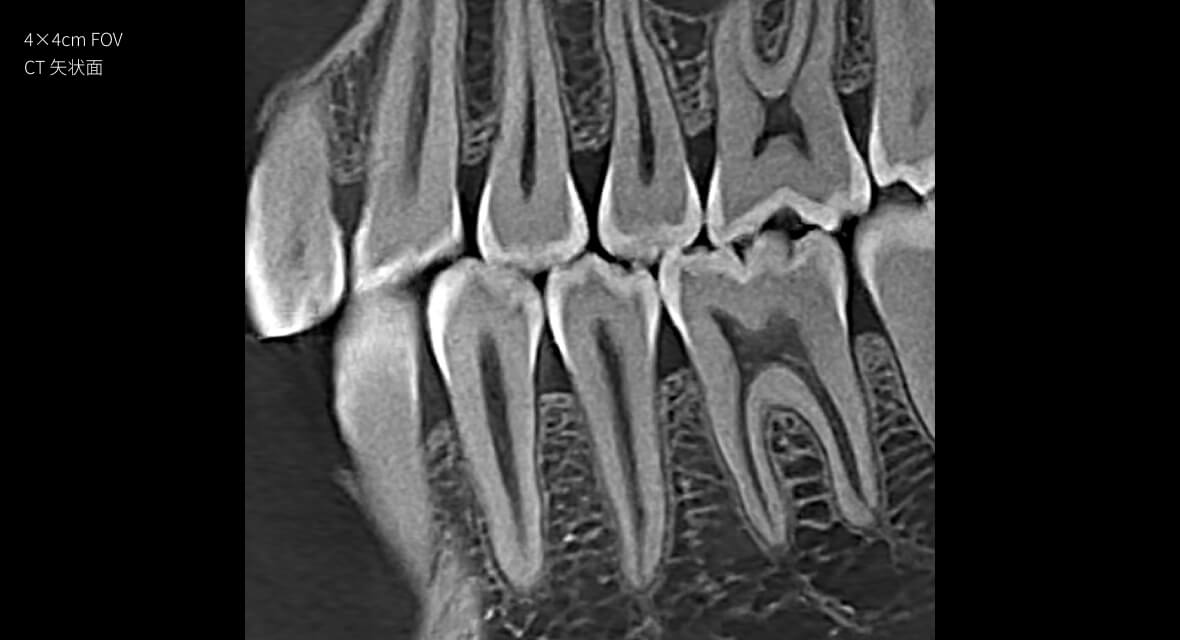

28lp/cm

高精准

Physics-driven系列伪影校正算法

实现高清精准成像

物理驱动

伪影校正算法